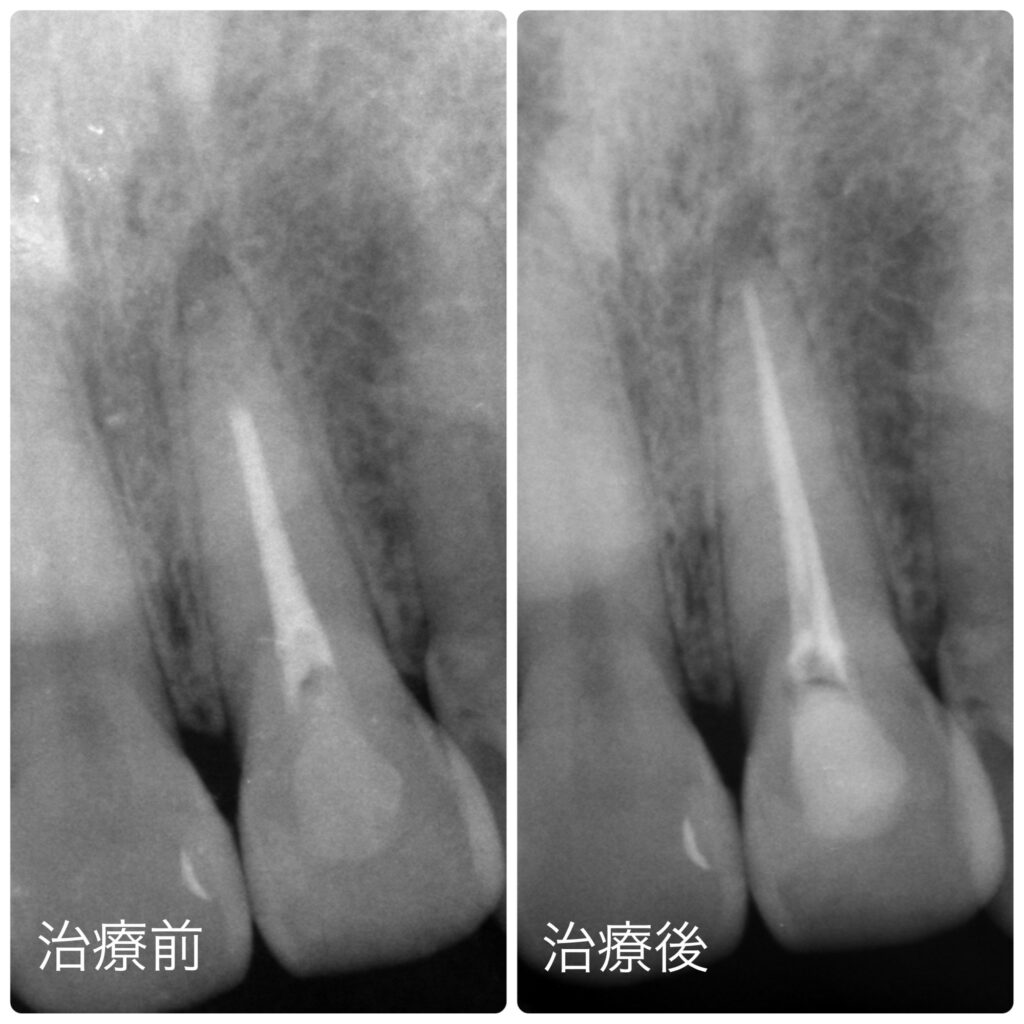

① 根の治療の確認・再治療

レントゲンで確認したところ、他院での過去の根の治療が不十分だったため、再根管治療を行いました。

見た目だけでなく、歯を長持ちさせるための土台を整えることが重要です。